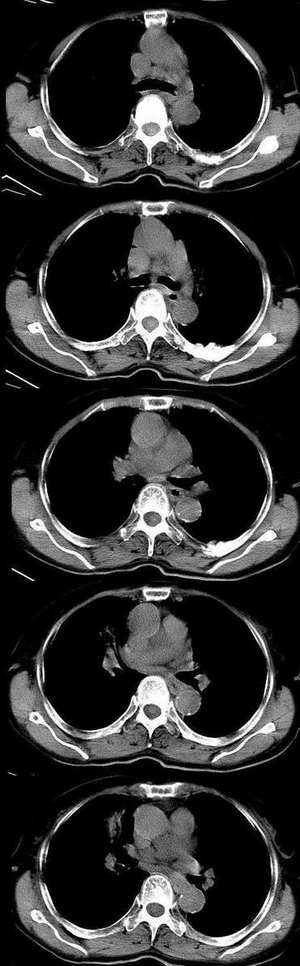

f73.反复胸痛、咳嗽5个月,加重1周入院。双肺呼吸音粗,闻及干湿性罗音。

慢支、肺部感染。

慢支合并感染,肺间质纤维化,肺气肿。右肺斑片阴影还是考虑慢性感染性病变---结核不除外,因为支气管分叉下淋巴结增大。

慢支炎,肺部感染,非局限性间质纤维改变,舌段可疑支气管扩张。中叶病变肿瘤待排。